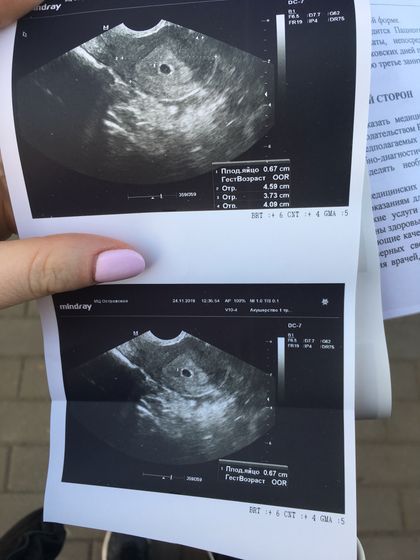

Всем привет) Сегодня была на узи, врач запугала что маленький хгч для этого срока и срок ставить не стала, сказала ждать, смотреть хгч в динамике и потом посмотрим развивается или нет. Рост хгч:29 дц (14 дпо) — 124; 32 дц (17 дпо) — 624; 34 дц (19 дпо) — 1709. На 35 дц (20 дпо) сделали узи, плодное яйцо 0,67 см, сердцебиение не слышно. Начало 5ой недели. Это нормально?